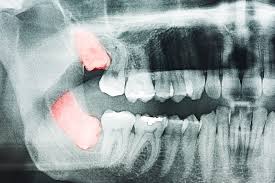

Bei einigen menschen brechen diese aber nicht durch das zahnfleisch hindurch, wodurch sie unter umständen schmerzen, schwellungen oder zahnfleischgeschwüre aulösen. Sich im kiefer befindende weisheitszähne Bei vielen menschen verursachen nicht durchgebrochene (retinierte) weisheitszähne keine beschwerden. Ein entzündeter weisheitszahn kann bei der entfernung, also während der op, weitere schmerzen verursachen. Darum müssen die fäden nach dem abheilen der wunden entfernt werden. Eine weisheitszahn op ist meist dann erforderlich, wenn diese nicht oder nur teilweise an die oberfläche gelangen und/oder wenn diese querliegen und so druck auf die nachbarzähne ausüben. Oben links jedoch sagte er, er müsste keine fäden ziehen da die wunde schon verheilt ist und keine fäden mehr zu sehen sind.alle wunden sehen im übrigen sehr gut aus! Weisheitszähne stehen zudem im verdacht, herzkrankheiten wie herzklappenfehler und rheumatische erkrankungen verursachen beziehungsweise verschlimmern zu können. Weisheitszähne brechen in der regel im alter zwischen 18 und 25 jahren als hinterste backenzähne durch. Wenn ein weisheitszahn durchbricht und im mundraum sichtbar wird, kann dies ganz schön schmerzhaft sein, besonders, wenn es sich um einen zahn im unterkiefer handelt. Die weisheitszähne (dens molaris tertius) zeigen sich in der regel erst nach dem 16. Wann ist eine weisheitszahn op notwendig. Aufgrund des komplett entwickelten gebisses finden die weisheitszähne innerhalb der zahnreihe keinen platz, um ungehindert durchzubrechen.

Aufgrund des komplett entwickelten gebisses finden die weisheitszähne innerhalb der zahnreihe keinen platz, um ungehindert durchzubrechen. Es hilft nicht, wenn man versucht, diese einfach zu ertragen, da dies sich eher negativ auf die heilung auswirkt und den körper schwächt. Dies kann zu zahnverschiebungen und beschädigung von nachbarwurzeln führen. Bereits durchgebrochene weisheitszähne sind die weisheitszähne schon voll durchgebrochen, lassen sich diese meist schnell und unkompliziert ambulant ziehen. Oft entdeckt der zahnarzt die weisheitszähne zufällig auf dem röntgenbild, solange der patient keine Denn solange die lokale betäubung wirkt, sollten sie auf mahlzeiten ganz verzichten. Sie können aber auch zu schmerzen, schwellungen, karies oder entzündungen am zahnfleisch führen. Lebensjahr, manchmal auch deutlich später. Weisheitszähne führen oft zu platzproblemen Wie lange eine wunde benötigt, bis sie verheilt ist, hängt aber auch maßgeblich davon ab, wie sich der patient nach einer weisheitszahn op verhält. Sehr harte sachen wie z.b. Nach etwa einer woche, in einigen fällen auch erst nach 10 oder mehr tagen, können die fäden gezogen werden. Bei vielen menschen verursachen nicht durchgebrochene (retinierte) weisheitszähne keine beschwerden.